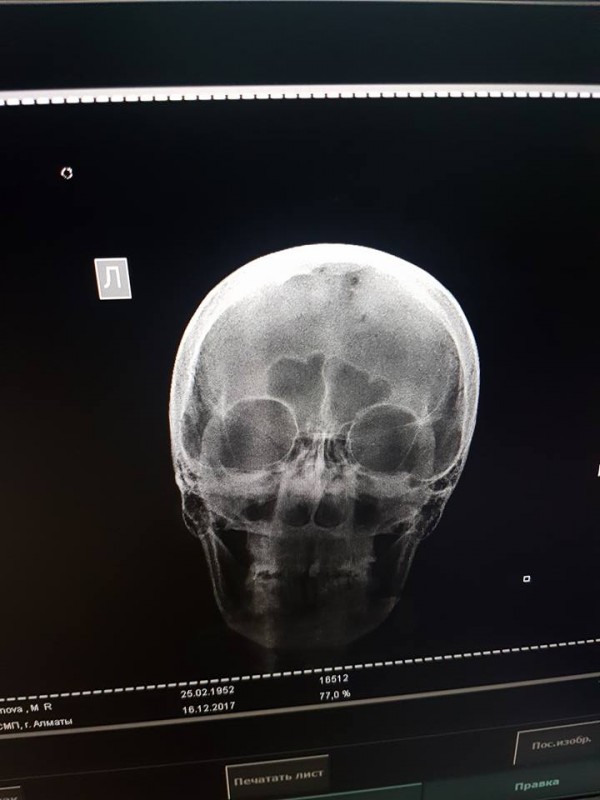

"В тяжелом состоянии доставили в БСМП, провели обследование, сделали МРТ. Закрытая черепно-мозговая травма, ушиб грудной клетки, компрессионный перелом позвоночника (7 позвонок). Требуется операция на позвоночник", - написала девушка.

Фото©Дина Нарбаева